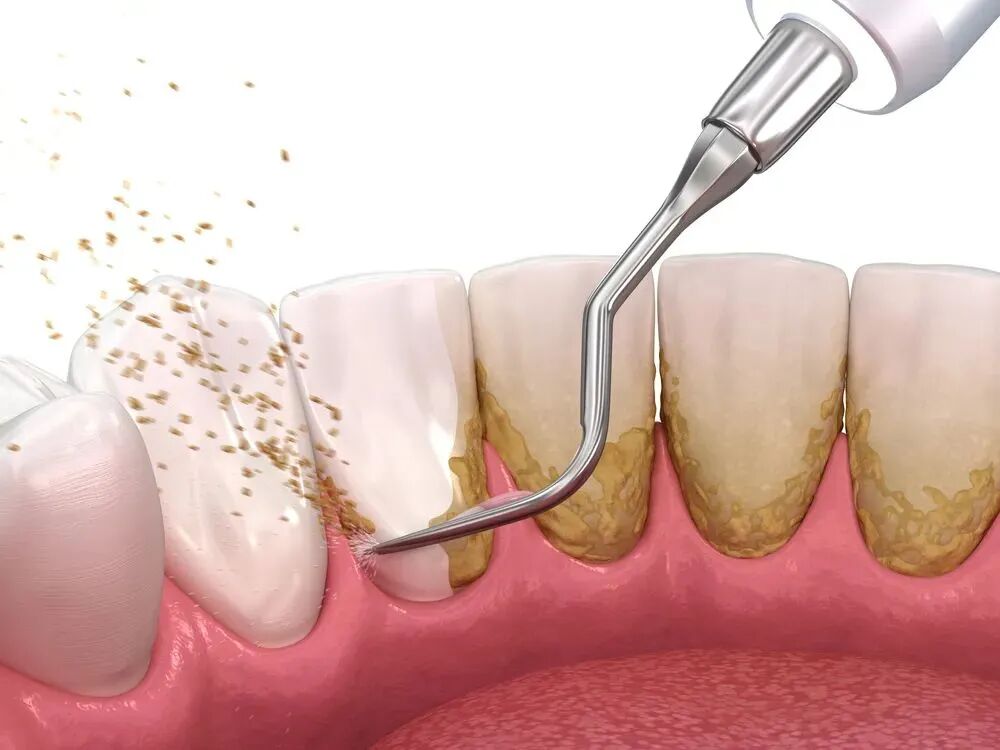

洗牙会破坏牙齿健康

图片

一些人担心洗牙会导致牙齿松动、破坏牙釉质等等,所以不愿定期洗牙。洗牙所用的工具是超声波机,它是采用平滑和无创的高频振动,使牙结石受到震动而松脱,而非磨除。喷砂也是采取高压水、气、砂同时作用的原理将牙齿表面的污物去除,只要操作正确,手法适当,洗牙是不会对牙齿有任何伤害的。

专家建议

一般建议半年或一年进行一次,具体根据个人生活习惯确定。如果是口腔卫生保持较好的人群一年进行一次即可;经常抽烟、饮酒或喜爱喝茶或含色素饮料的人群,或本身有口腔疾病如牙周炎的情况,一般建议半年洁牙一次。